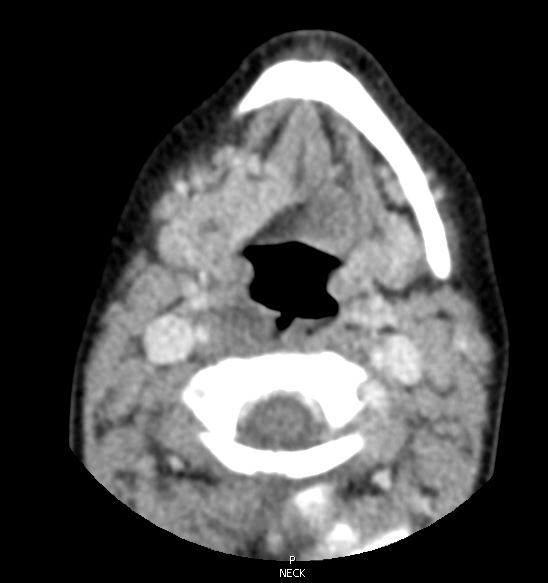

Diagnostic tests. The patient was sent for a stat soft-tissue neck radiograph, which showed air in the retropharyngeal space with thickened soft tissues, concerning for retropharyngeal abscess (Figure 1). He was sent to the emergency department, where a computed tomography scan was performed, the results of which showed a mucosal tear in the retropharyngeal soft tissues at the C2 level with associated retropharyngeal gas (Figures 2 and 3). He was admitted to the pediatric hospital for further evaluation and management.

Figures 2 and 3. Computed tomography imaging of the neck showing a mucosal tear at the C2 level with air in the retropharyngeal space.